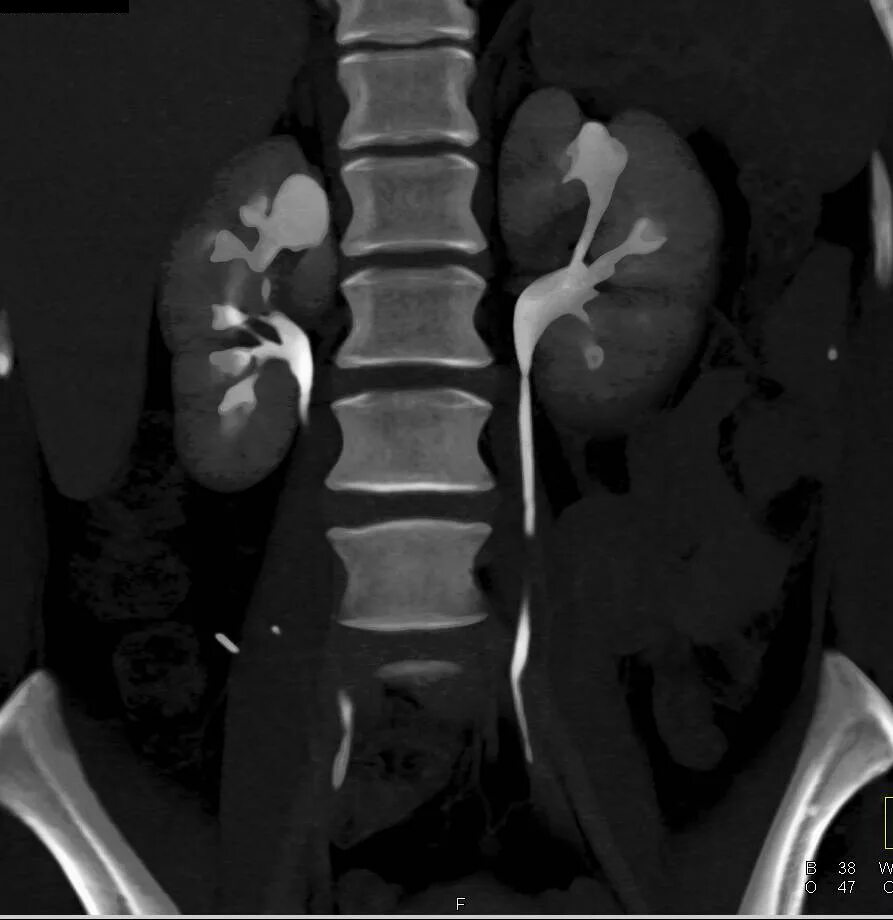

Пиелонефрит кт